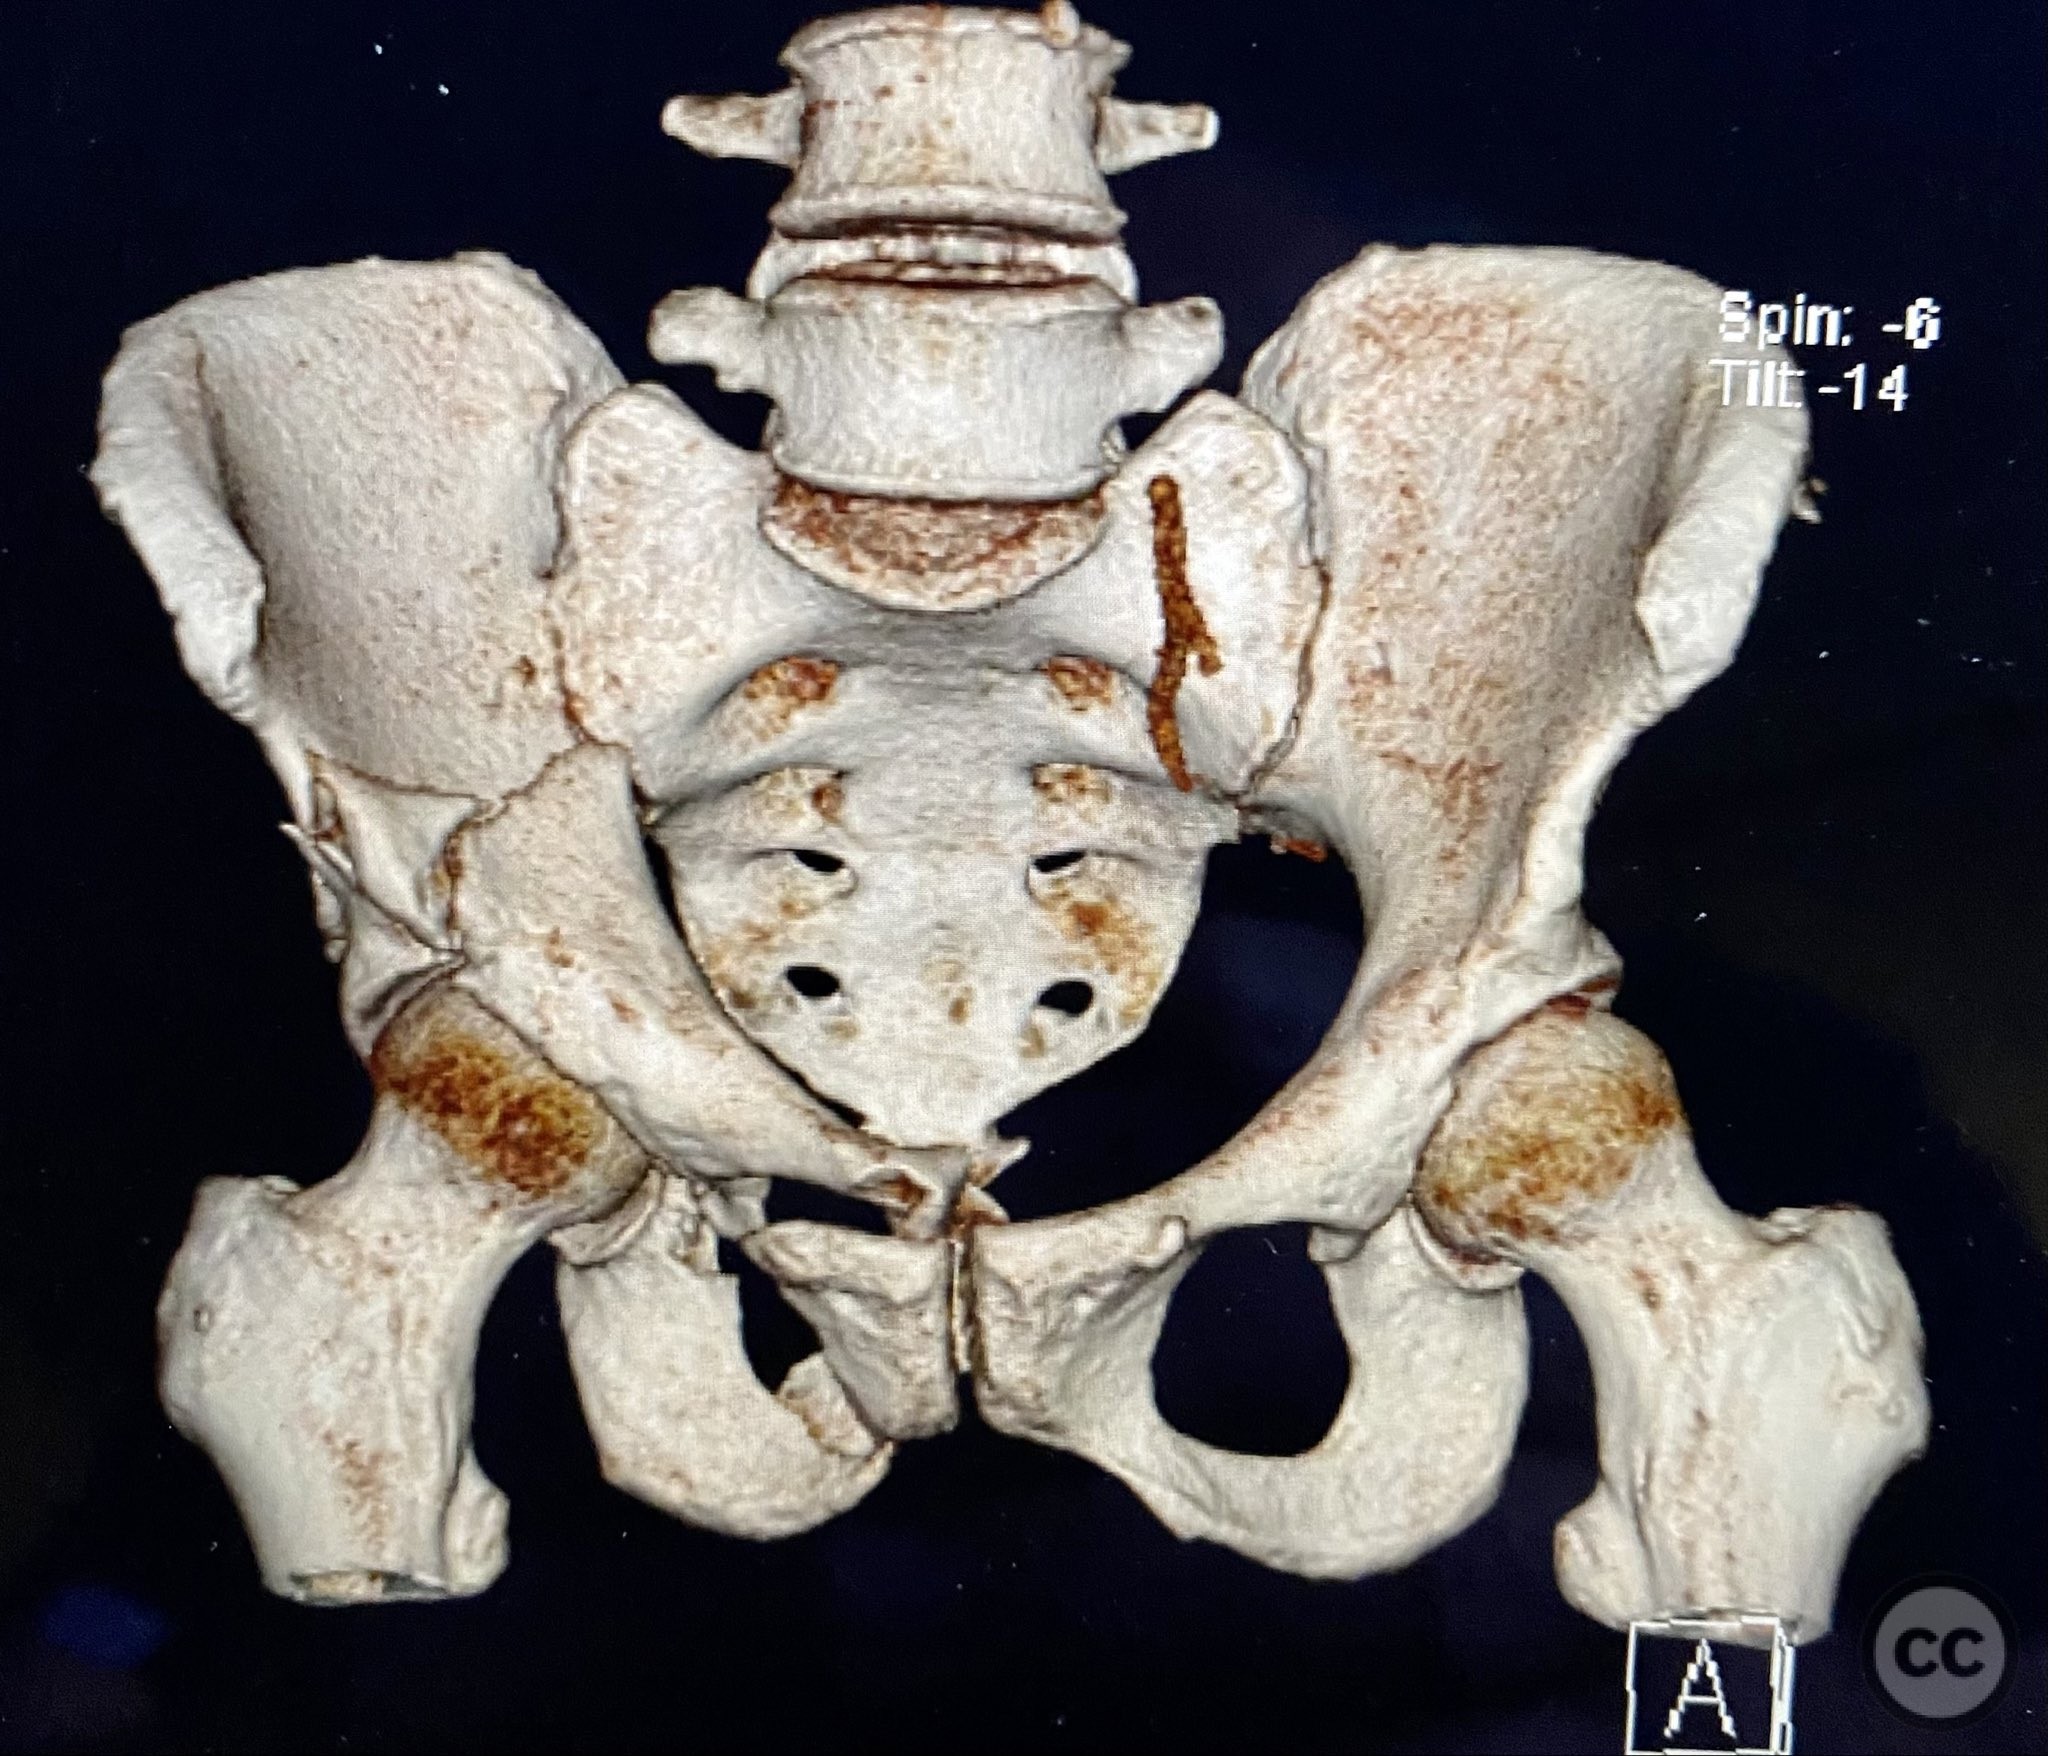

Clinical and radiological findings:  The patient sustained a complex both column acetabular fracture, AO/OTA 62C1, characterized by several large columnar fragments, an independent anterior inferior iliac spine (AIIS) fragment, a notable dome fragment predominantly attached to the posterior wall (PW) fragment, and a distinct parasymphyseal injury zone. Initial application of a pelvic binder resulted in increased displacement of the fracture fragments. Preoperative imaging, including surface renderings and multiplanar CT, demonstrated the independent AIIS fragment, detailed cortical surfaces, and the orientation of fracture planes. The majority of the acetabular dome was associated with the PW fragment, a critical detail for surgical planning and reduction.